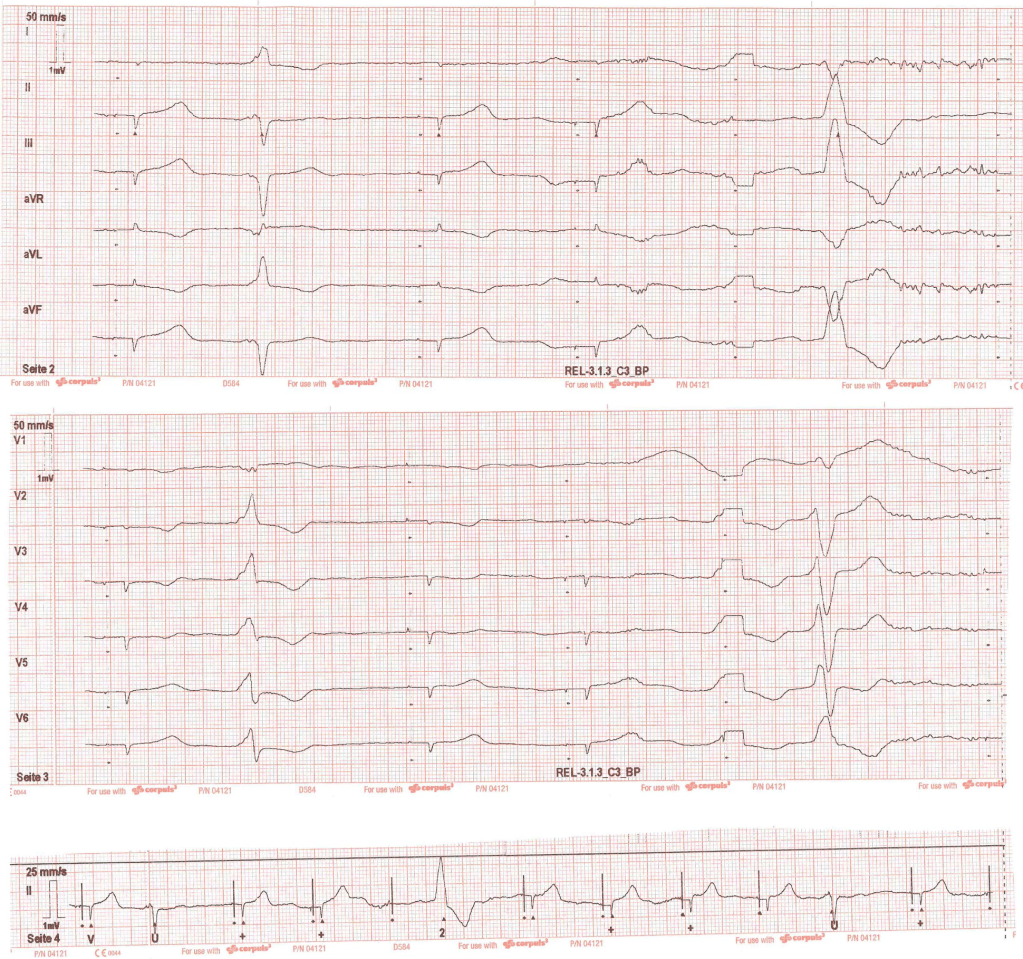

Du leitest nun folgendes 12-Kanal-EKG ab:

Du lässt den RTW an einer sicheren Stelle anhalten, ihr schaltet zur besseren Sichtbarkeit Blaulicht ein. Nun leitest du erneut ein 12-Kanal-EKG ab, dieses zeigt:

Du bewertest das EKG folgendermaßen:

Signifikante ST-Hebungen in III, aVF und II.

Im Nachhinein nehmt ihr das 1. EKG noch einmal extra-nerdig unter die Lupe:

Es liegen tatsächlich (nicht signifikante) ST-Hebungen in III, aVF und II vor. Diese entsprechen zwar nicht den STEMI-Kriterien, können aber dennoch hinweisgebend auf einen akuten Koronarverschluss sein. Solche EKGs werden okklusiver Myokardinfarkt (OMI) genannt und diese Patienten benötigen ebenfalls eine umgehende Herzkatheteruntersuchung.

Außerdem sind auf der „gegenüberliegenden“ Seite ST-Senkungen zu sehen (in diesem Fall in I und aVL). Man sollte bei Detektion von (nicht-signifikanten) ST-Hebungen immer nach kontralateralen ST-Senkungen suchen, die die Diagnose eines OMI unterstützen können.

Weiterhin sieht man in der Ableitung III ein biphasisches T (roter Kreis). Dieses kann ein Hinweis auf ein akutes Koronarsyndrom mit passagerem Koronarienverschluss sein, siehe auch hier.

Zudem ist der vierte Schlag eine VES, in der sich ST-Hebungen in III und aVF zeigen und auch die ST-Negativierungen in I und aVL deutlich zutage treten. Da ihr euch nicht sicher seid, ob das in VES überhaupt zu verwerten ist, macht ihr eine Internetrecherche und findet heraus, dass das sehr wohl möglich ist. Siehe im Smith ECG Blog

Dort steht u.a. (Achtung: Extra-nerdig), dass bei rechtsschenkelblockartiger Konfiguration der VES die ST-Strecke auf der gegenüberliegenden Seite von R´ sein sollte, d.h. gesenkt. Aber in diesem Fall ist sie erhöht als konkordante ST-Hebung. Dieses ist ein sehr spezifisches Zeichen eines OMI.